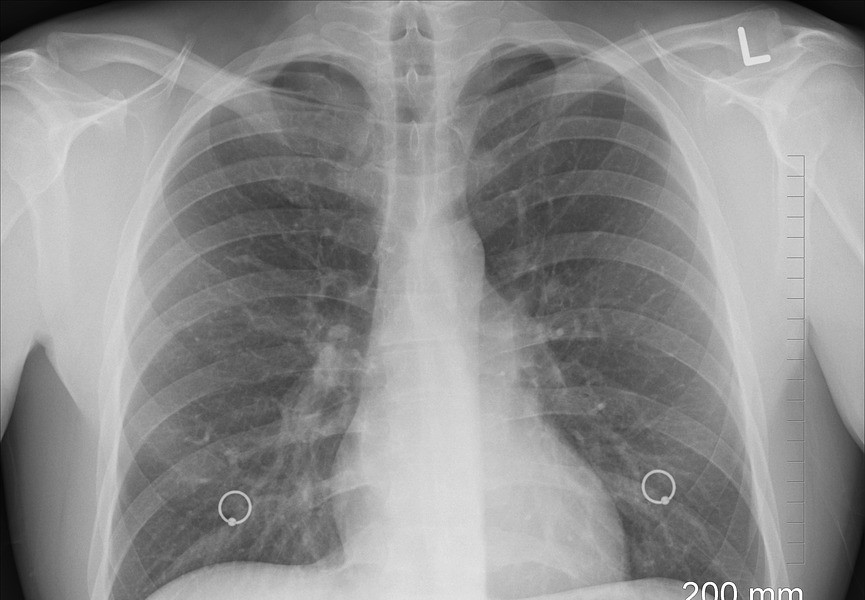

No hay aumento de casos de tuberculosis en República Dominicana, afirma presidente de la Sociedad Dominicana de Neumología

Hoepelman explicó que solo se están detectando nuevos casos debido a los nuevos métodos moleculares que se está usando para la detección de la enfermedad, y porque ahora se están haciendo pruebas en l…